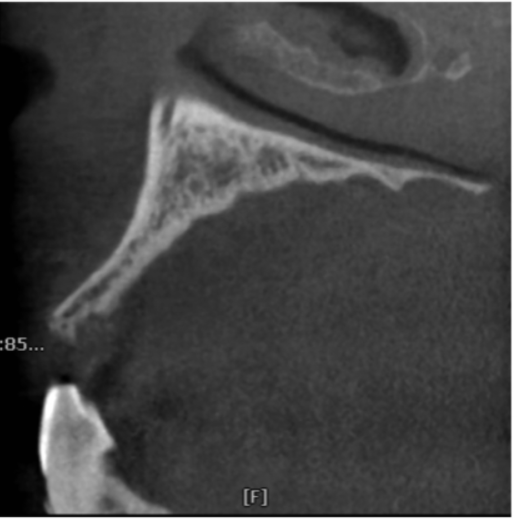

图12 术前CBCT片矢状位显示上颌前牙区的牙槽骨形状细小

图13 术前CBCT片矢状位显示上颌前牙区的牙槽骨形状极度弯曲

图14 术前CBCT片矢状位显示在下颌前牙区的牙槽骨形状非常细,上颌前牙区的牙槽骨高度不足

图15 术前CBCT片矢状位显示下颌前牙区的牙槽骨形状细小而且中份骨质较致密